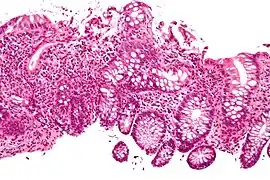

Cryptitis. H&E stain.